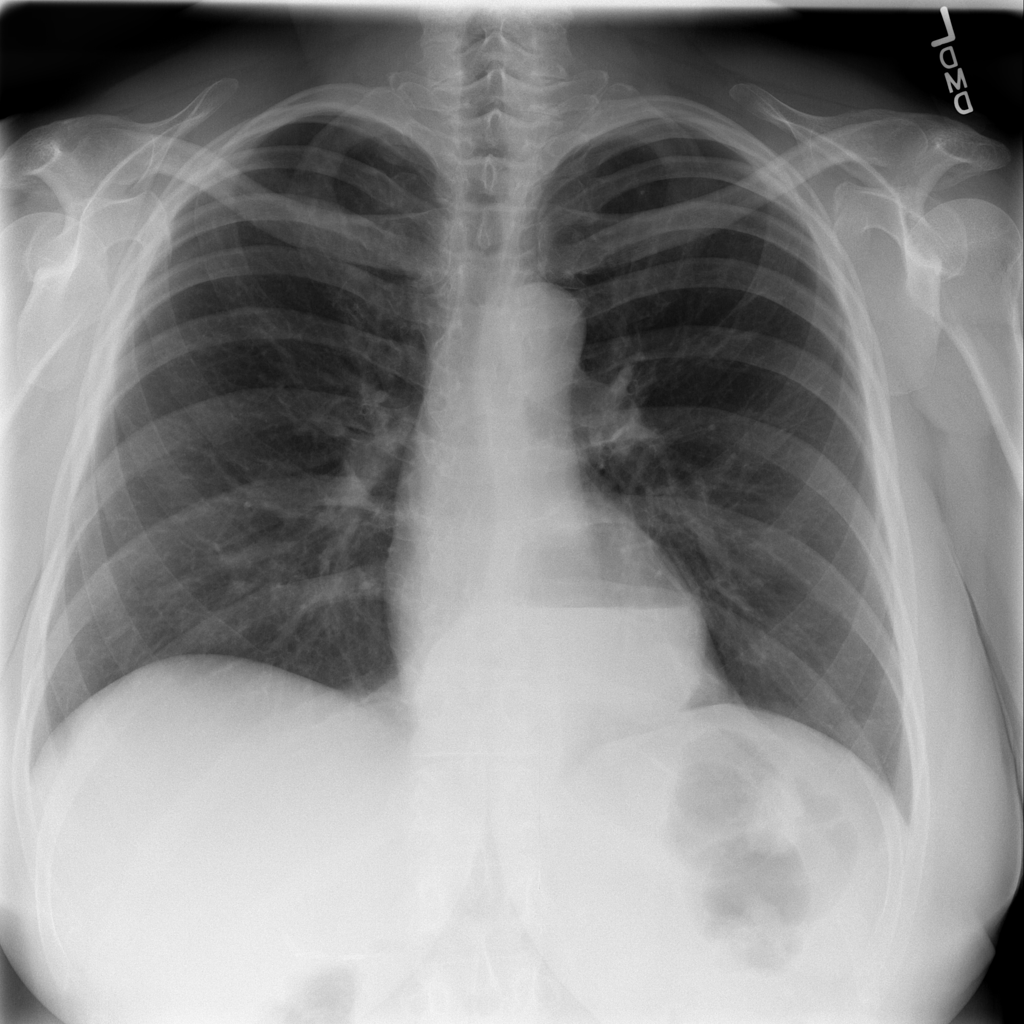

PAT-C048 · IMG-001Hernia

PAT-C048 · IMG-001

PA